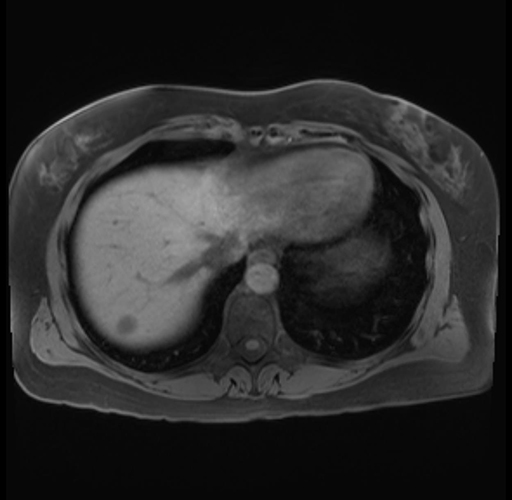

Imaging Analysis

Look through the patient's CT scan to identify any areas of concern for the necessary procedure.

Based on your CT findings, which issue(s) are present and would give reason for "planned slowing down moment(s)" in this case?

Considering a standard distal pancreatectomy procedure, what step(s) of the operation would you do differently in this case?